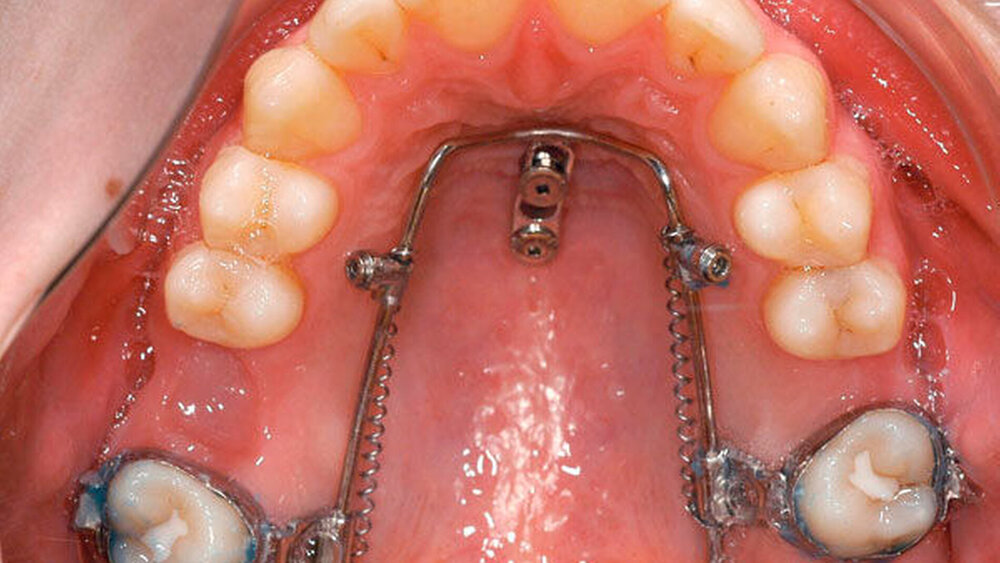

Mini-Implantate und Mesialslider in der Therapie